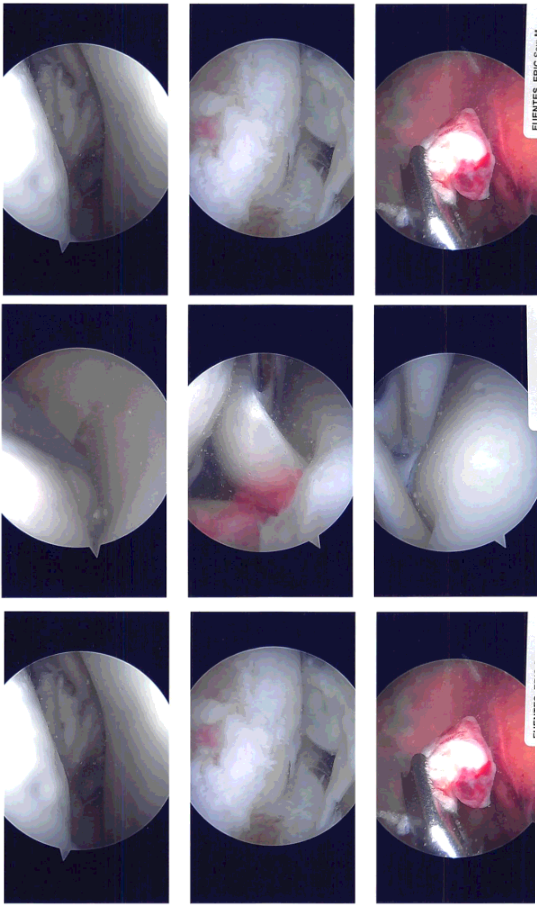

Examination of the patellofemoral compartment showed no arthritic changes. Examination of the medial patellofemoral compartment showed grade 3 to grade 4 change in a small patch over the medial femoral condyle.

The meniscus showed an inferior flap over the posterior horn, which was removed with the shaver. There was no ramp lesion or meniscal tear. The scope was entered into the Intercondylar notch where the ACL was found to be torn. The ACL was debrided with the use of a shaver. The PCL was intact.

The medial wall of the lateral femoral condyle was cleaned and debrided for identification of the footprint of the ACL. The tibial footprint of the ACL was also debrided. The arthroscope was entered into the lateral femoral condyle and lateral tibiofemoral compartment.

It showed grade 3 to grade 4 arthritic changes over a third of the femoral condyle. Also, there was a bad tear in the lateral meniscus, which was extending from the mid body to the posterior body and the posterior Hom across the popliteal hiatus.

Intraoperative Arthroscopy Images